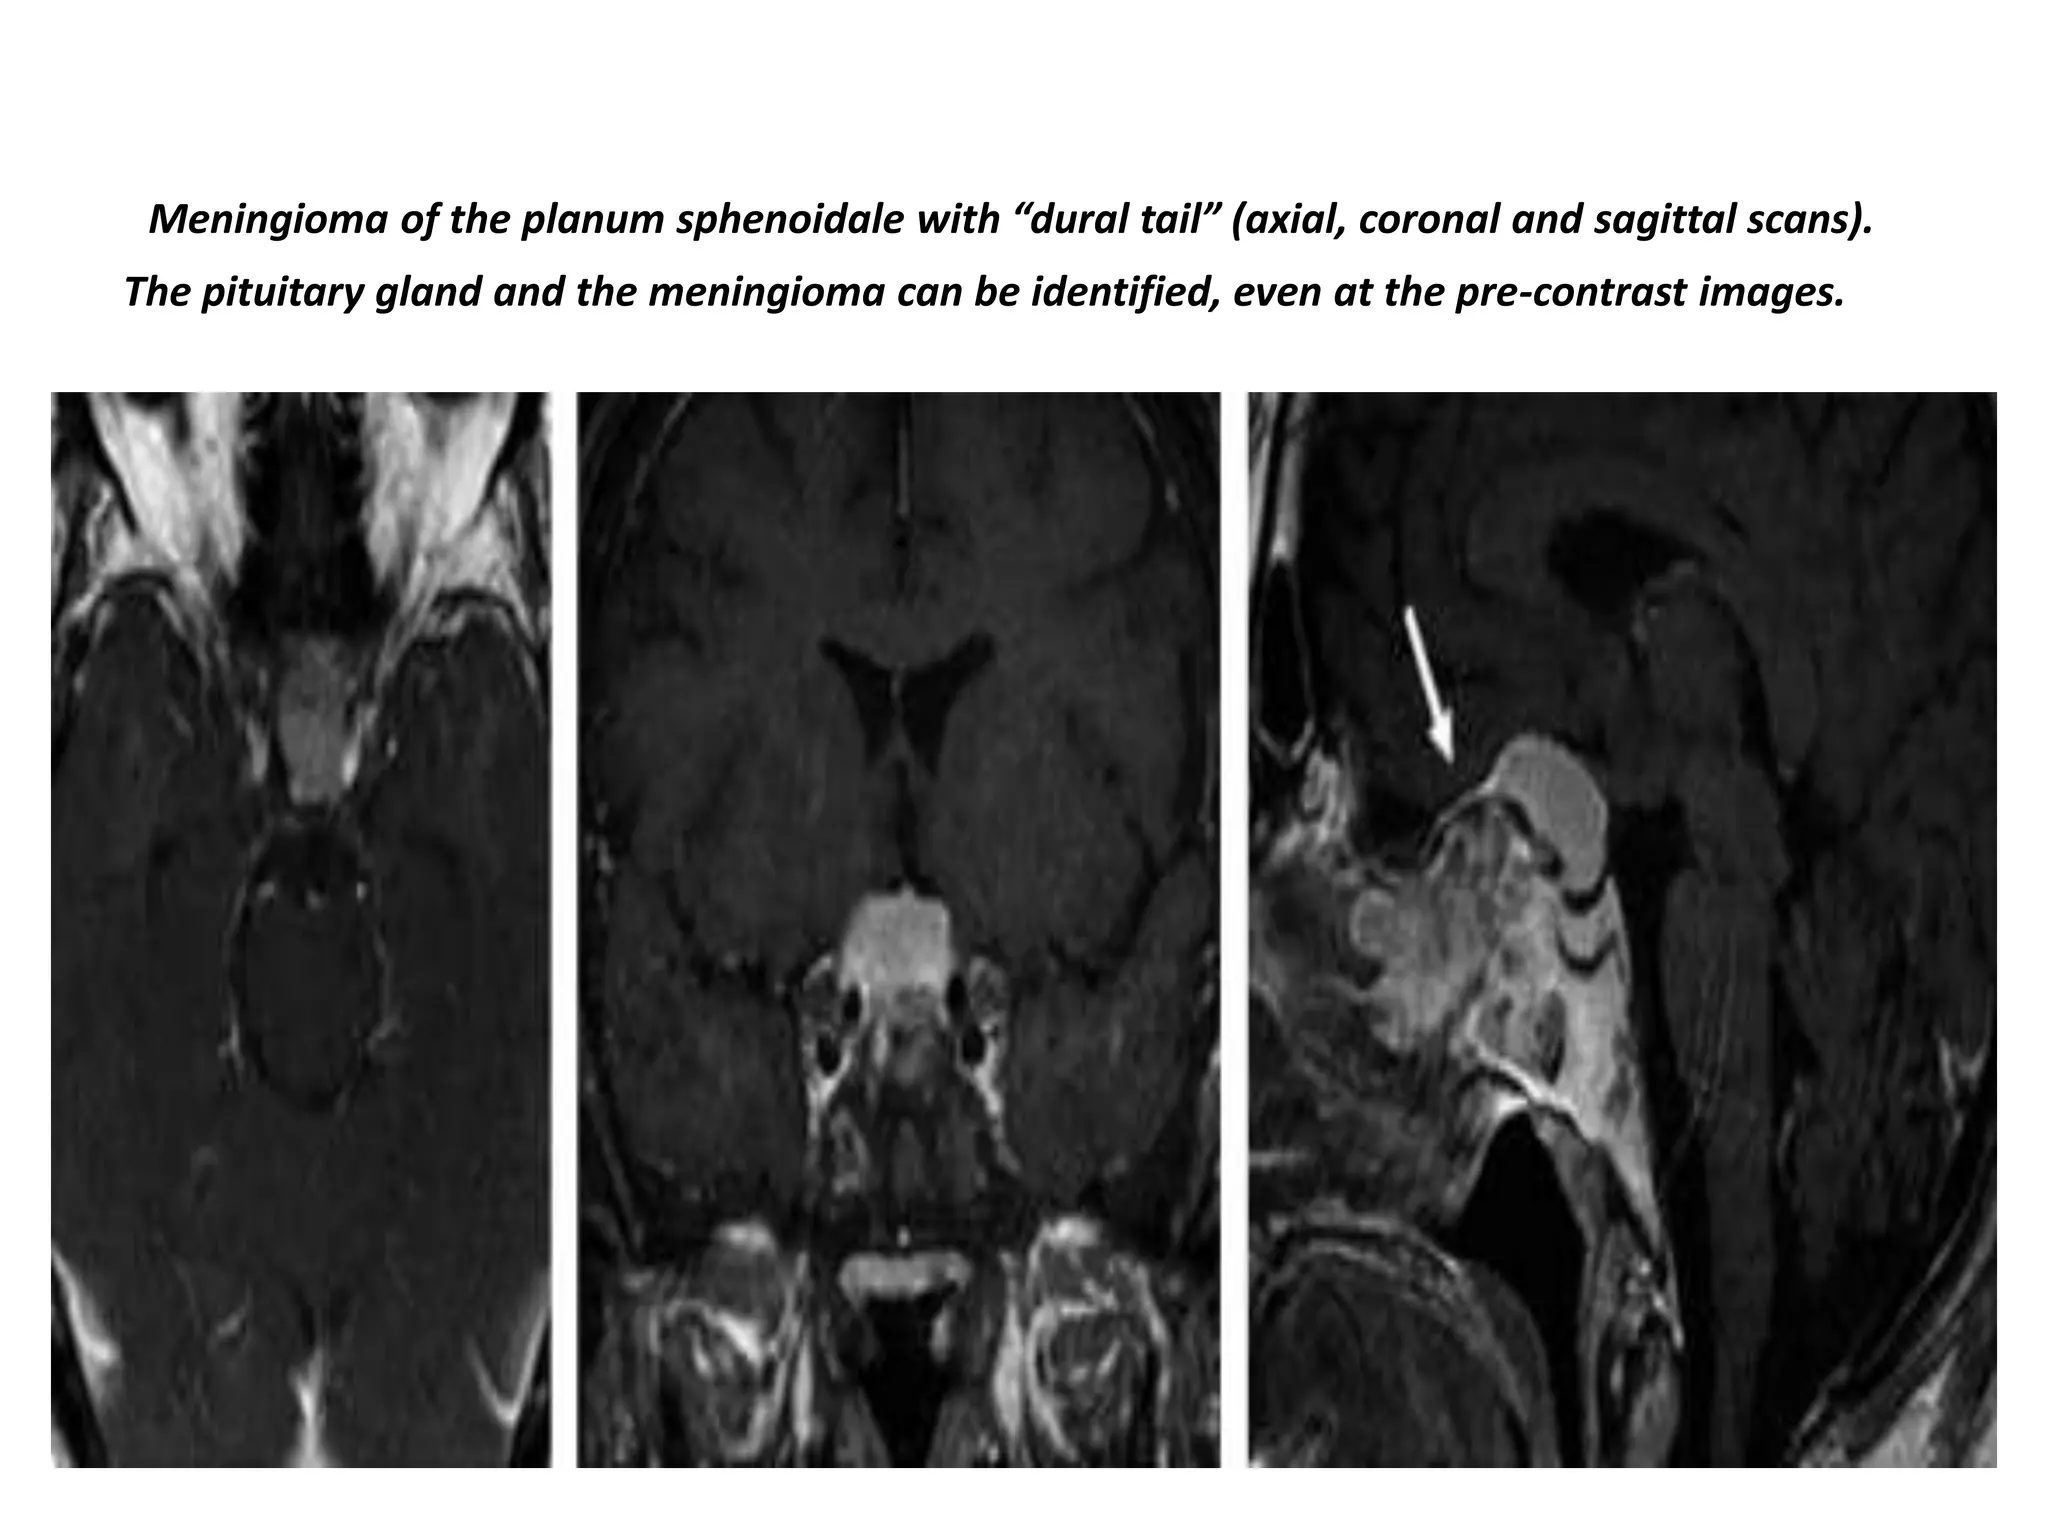

Meningioma of the planum sphenoidale with “dural tail” (axial, coronal and sagittal scans).

The pituitary gland and the meningioma can be identified, even at the pre-contrast images.